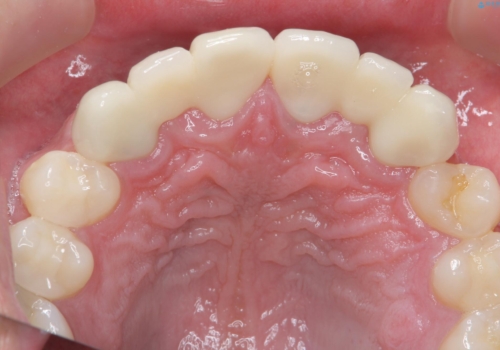

バラバラに位置している前歯の位置を矯正治療で修正してからブリッジを装着しています。

矯正治療によって事前に歯の位置を修正しているため、ダミーの歯の大きさも調整し、自然な仕上がりにしました。また、犬歯のねじれを治してから削っているため、神経をとらずに歯の形を整えることができました。